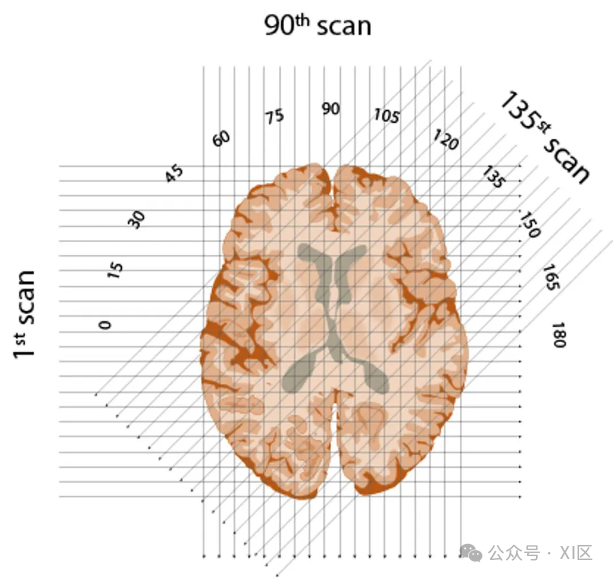

扫描方式:采用“平移-旋转”式。X射线管与探测器作为一个整体,先进行一次直线的平移扫描,获取一组平行光束的投影数据;然后旋转1度,再次平移,如此反复,直至完成180度的数据采集。

X射线束穿过大脑的每一个“切片”,这些X射线束的方向是从1度到180度,呈半圆形排列。

计算每次X射线穿过物体后的强度,然后通过强大的算法进行反向推算,就能够构建出一幅图像。